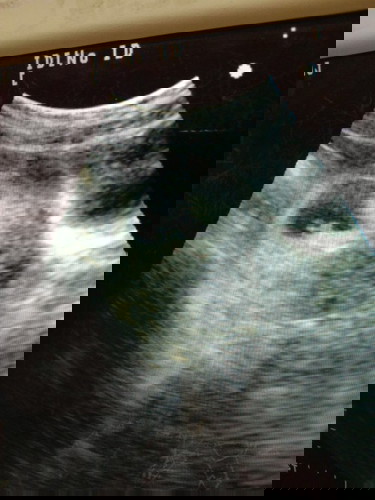

ซาว 7w ท้องสองจ้าา

ซาว 7wค่า เห็นน้องเเล้วเเต่ยังไม่ได้ยินเสียงหัวใจน้องเลยค่า นัดอีก สองอาทิตย์. เเม่ๆกี่ w. กันเเล้วคะ